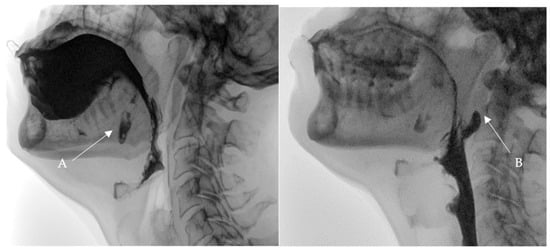

Following these findings, the ENT specialist reassessed the patient and confirmed the presence of bilateral diverticula in the buccal area and posterior pharyngeal walls, in alignment with the VFSS findings. The two diverticula were located on the right and left side inferiorly in the buccal area (Figure 3) and (Figure 4), and two were located on the right and left side superiorly in the oropharynx area. (Figure 5) and (Figure 6).

Figure 3. Selected still image captured during the FEES assessment: arrow heads pointing to the opening of a diverticulum located in the left inferior aspect of the buccal area.

Medicina 60 01628 g003

Figure 4. Selected still image captured during the FEES assessment: arrow heads pointing to the opening of a diverticulum located in the right inferior aspect of the buccal area.